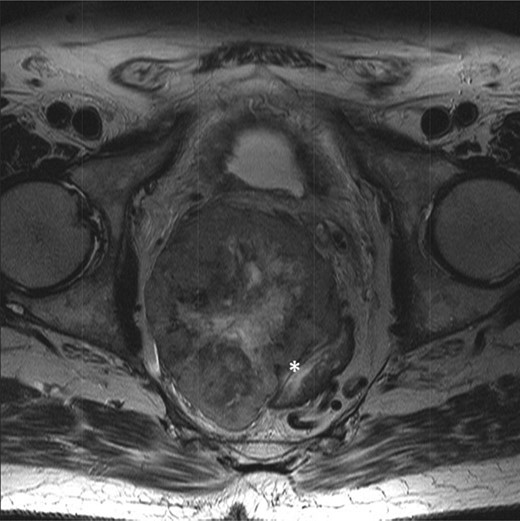

An elderly man in his seventies presented to the Urology department with two episodes of acute urinary retention. There were no rectal symptoms and rectal examination revealed an enlarged prostate. He underwent a laser transurethral resection of prostate during which a large palpable pelvic mass was noted. The subsequent urgent MR pelvis revealed a large tumour in the mesorectum arising from the anterior rectum 10 × 8.5 cm (Figs 1 and 2). A transrectal ultrasound and biopsy were performed; histology revealed a spindle cell tumour, with positive immunostains for CD117 and DOG1 with 5 mitoses per 50 high power fields. This was confirmed to be a locally advanced high-risk GIST.

T2-weighted axial showing the same mass lying adjacent to the anterior wall of the rectum (*).